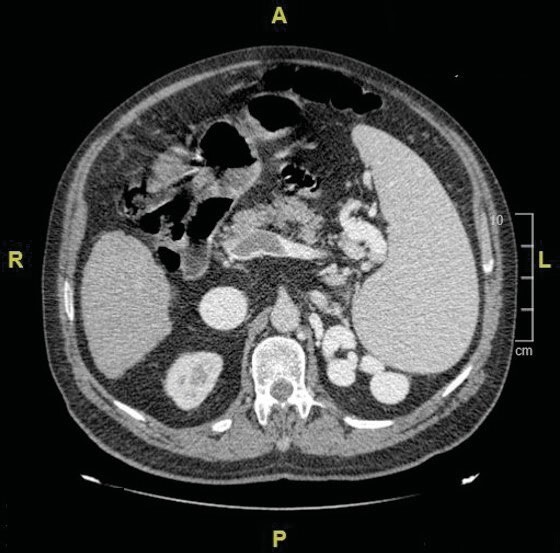

It is important to make the differential diagnosis of restrictive changes associated with hepatic hydrothorax or hepatopulmonary syndrome seen in the later stages of chronic liver diseases and restrictive changes associated with interstitial lung disease. Lymphocytic interstitial pneumonia (LIP) is in the rare idiopathic interstitial pneumonia subgroup of interstitial lung diseases. LIP is a rare disease, and its incidence is unknown. LIP is characterized by infiltration of the alveolar interstitium with lymphocytes, plasma cells, and histiocytes. The etiology of LIP includes idiopathic causes, rheumatological diseases, immune deficiencies, viral infections, and drug-related causes. Chronic liver diseases are also rarely included in the etiology of LIP. A 75-year-old male patient who was followed up for liver cirrhosis presented with dyspnea. He had hypoxemia in the arterial blood gas. In the thorax and abdominal computed tomography, irregular reticulations in bilateral lungs, ground-glass opacities, and scattered air cysts in both lung parenchyma, chronic liver parenchymal disease, splenomegaly, chronic portal vein thrombosis were determined. Clinical and radiological changes in the patient were evaluated in favor of interstitial lung disease. Although histopathological diagnosis could not be made, the patient whose radiological pattern was compatible with LIP was evaluated together with clinical findings and was accepted as lymphocytic interstitial pneumonia. He was evaluated in terms of diseases that could cause LIP. He was accepted as LIP due to chronic liver disease. Although histopathological examination is the gold standard for the diagnosis, a biopsy could not be performed in our case. Radiological and clinical findings were considered sufficient for the diagnosis of LIP. Chronic viral hepatitis and cirrhosis are also present in the etiology of LIP. Our case is presented as an example in the literature because it is a case of LIP due to chronic liver disease, and it is rare.